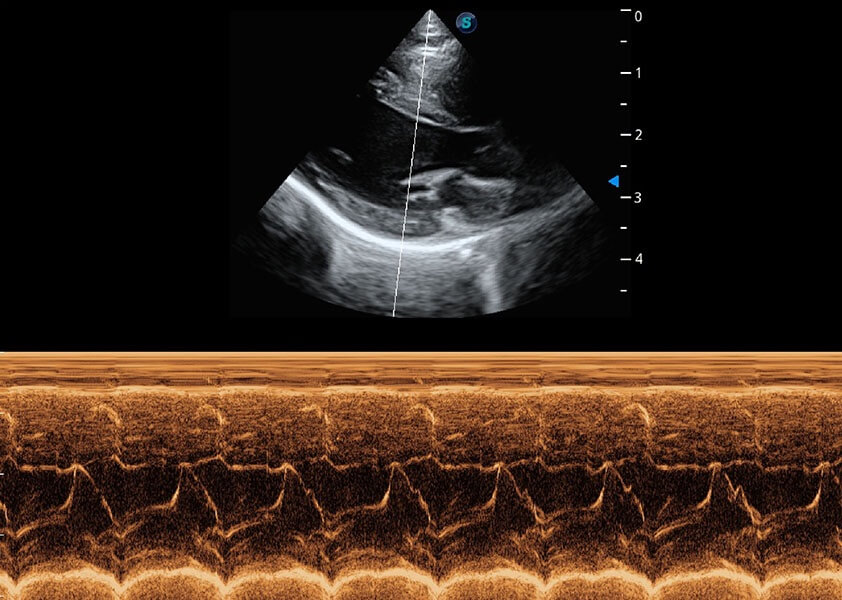

心脏解决方案

ProPet 60 配备了丰富的心脏探头群、先进的成像技术和专业的心脏测量工具,可帮助动物医生为不同体型和生理结构的动物提供心脏和心肌功能的全面评估。

• TDI 组织多普勒成像

实时用颜色表示心肌组织运动,观察和定量组织的运动情况,对快速检测与评估心肌的灌注和活性、电传导及心肌收缩和舒张功能等均能提供重要的诊断信息。

• AMM 解剖M型

通过360度任意调节3条M型取样线,在同一心动周期上观察心脏不同位置的运动曲线,得到准确的心功能测量数据,有效评估心肌运动及左心室功能。

优异的基础图像

(犬)心脏组织多普勒

(犬)乳头肌短轴

(猫)二尖瓣M型